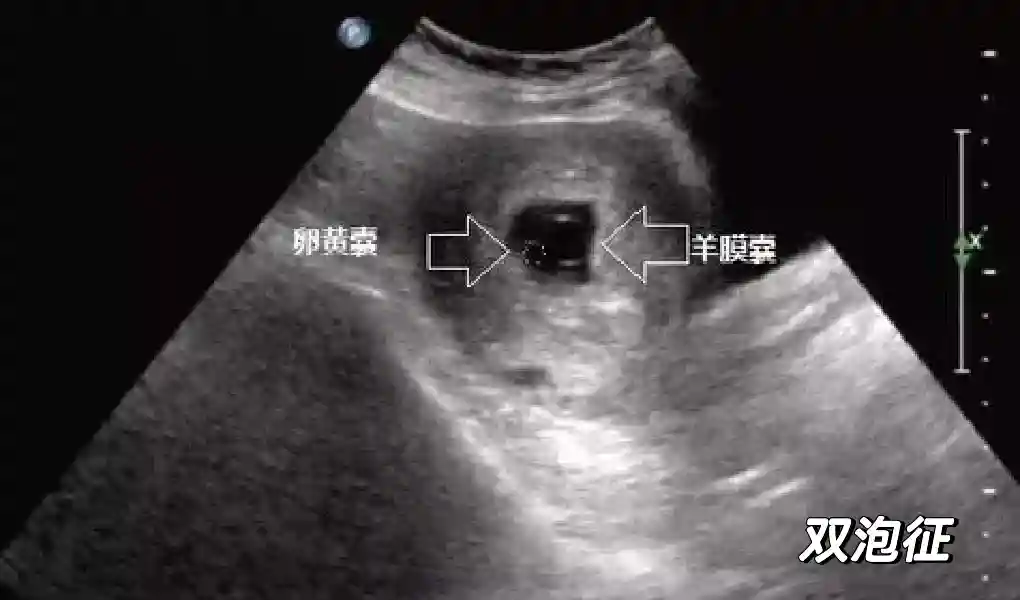

1️⃣妊娠囊:早期妊娠囊:正常妊娠囊位于宫腔上段,表现为宫腔内圆形或椭圆形的无回声区,周边为完整的、厚度均匀的强回声环,强回声环厚度≥2mm,强回声是妊娠绒毛的回声,随着妊娠囊的增大,形成特征性的“双环征” ,10周以后消失。正常的妊娠囊增长速度是平均 1 mm /d。